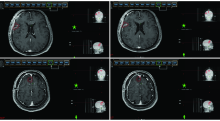

| [2] | 赵永瑞, 高莹, 陈怡东, 徐建堃. 基于直线加速器的分次立体定向放疗对小体积脑转移瘤的有效性及安全性[J]. 国际肿瘤学杂志, 2023, 50(3): 138-143. |